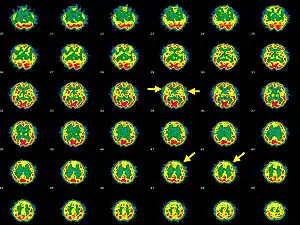

| Brain SPECT transaxial images of a patient afflicted with Hashimoto's encephalopathy. | |

- Single photon emission computed tomography shows focal and global hypoperfusion (75% of cases)